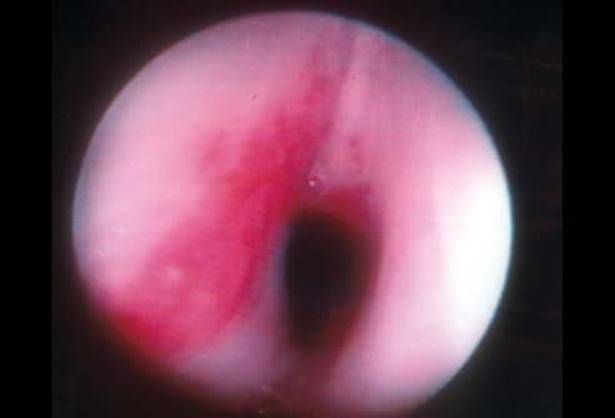

Third and fourth BAs can be grouped together as “pyriform sinus tracts.” Pyriform sinus tracts should be considered in any child with recurrent left neck abscesses or suppurative thyroiditis.8 Direct laryngoscopy with identification of a fistulous opening confirms the diagnosis (Fig. 19.2).

Figure 19.2 Endoscopic localization of a pyriform sinus tract.